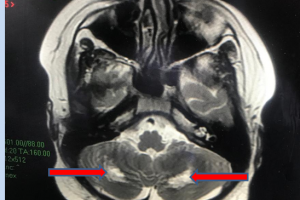

Vừa qua Bệnh viện Nhi Đồng Thành Phố tiếp nhận một trường hợp trẻ H. T. K. L. 2 tuổi, nữ, ngụ ở Vĩnh Lộc B, Bình Chánh, Thành phố Hồ Chí Minh. Khai thác bệnh...